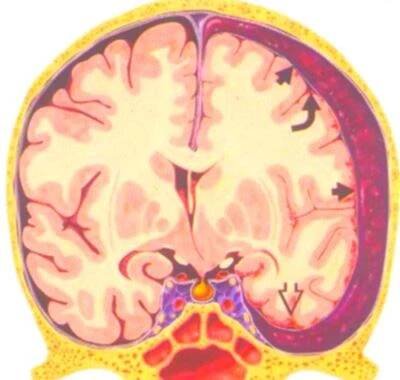

Subdurální hematom představuje závažnou komplikaci při poranění hlavy, ke kterému nejčastěji dochází při autonehodách, pádech nebo jiných úrazech. Jedná se o druh traumatického poranění mozku, při kterém krev z poraněné cévy vytéká pod tzv.

Michael Schumacher má několik otoků na mozku, jeden se v úterý podařilo lékařům odstranit. Co je subdurální hematom? Druh traumatického poranění mozku, při kterém se přetrhají žilky v ochranné membráně mozku a  dojde k otoku. Krev se hromadí mezi tvrdou plenou mozkovou a povrchem mozku a způsobuje tlak na mozkovou tkáň. Mezi symptomy patří bolest hlavy, zvracení, poruchy vědomí a někdy i zhoršení intelektu.